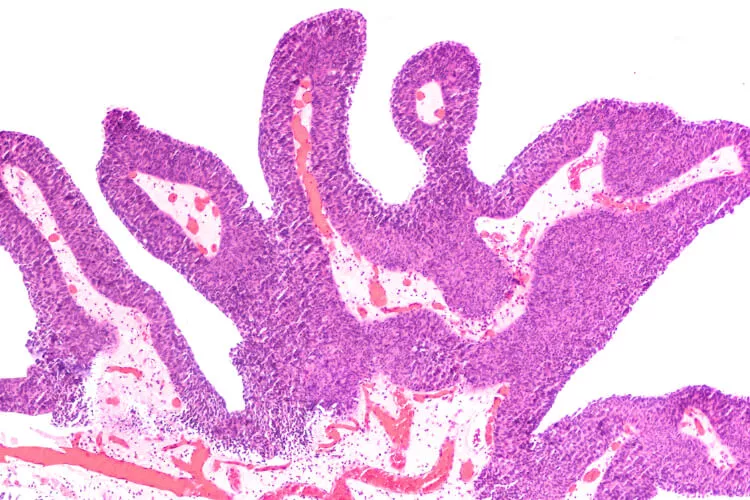

Živou debatu v sekci Rapid-fire odstartoval prof. MUDr. Marek Babjuk, CSc., prezentací kazuistiky fragilního 86letého pacienta (celoživotního kuřáka) s několika komorbiditami (včetně kardiovaskulárních), u nějž již v roce 2019 na jeho pracovišti po zjištění 5 papilárních tumorů (velikosti 4–10 mm) nízkorizikové klasifikace Ta LG/G1 (uroteliální karcinom) provedli jejich transuretrální resekci (TURBT) a instilaci mitomycinem C, a kterého opětovně přijali po 7 měsících poté, co u něj cystoskopie odhalila 6mm papilární lézi v zadní stěně močového měchýře a obdobný 5mm nádor na jeho levé straně. Poté M. Babjuk oslovil sledující experty z předních světových urologických pracovišť, aby se vyjádřili k terapeutickým možnostem u takového případu. Přiklonit se k standardnímu řešení (TURBT a intravezikální léčba), nebo ke konzervativnějšímu přístupu s aktivním sledováním nádoru a fulgurací?

Možnost vyjádřit se přes webkameru a mikrofon dostává prof. Wassim Kassouf z McGill University v Kanadě – ten odkazuje na známá a publikovaná fakta (Matulay JT et al., BJU Int 2020; Kim JK et al., J Cancer 2017; Oliver K, Bosset JF, Urol Oncol 2015; Herr HW et al., J Urol 2007), a sice, že až 60 % karcinomu močového měchýře je nízkorizikových (LG Ta) s rekurencí ve 30–60 % případů, avšak dobrou prognózou (velmi nízké riziko progrese – 3 % do 10 let a nádorově specifická mortalita < 1 %). Dle jeho názoru tak jde o malignity, které by nemusely být až tak velkou zátěží pro zdravotnický systém a společnost – terapie by u nich nemusela být až tak intenzivní (bez zhoršení parametrů přežití pacientů), jak se ostatně děje i u nízkorizikových karcinomů prostaty či malých nádorových lézí na ledvinách (SRM). A obrací pozornost kolegů ve studiu i u obrazovek všude po světě mimo jiné na práci autorů Herr HW et al., (J Urol 2002), která ukazuje, že urologové dovedou u nízkorizikových karcinomů močového měchýře velmi přesně predikovat rizikovost rekurentní malignity – v citované práci bylo cytoskopickou analýzou 144 rekurentních papilárních tumorů správně klasifikováno jako TaLG až 99 % lézí. Obdobně tomu bylo v novější (prospektivní) studii (Mariappan P et al., Urology 2017) – v ní byla predikce nízkorizikového nádoru u 248 subjektů správná v 88 % případů (a až u 88 % analýz, pokud se v potaz braly jen léze menších rozměrů). W. Kassouf též zmiňuje, že ačkoliv se TURBT obecně považuje za menší a poměrně bezpečný výkon, jsou zaznamenávány komplikace při cca 5 % zákroků (Collado A et al., J Urol 2020), jako například perforace, krvácení, opakované hospitalizace, reoperace a jiné dopady na kvalitu života pacientů (nehovoře o nákladech), což jistě není možné podceňovat, speciálně u starších a křehčích nemocných. Data autorů Pereira JF et al. (Urology 2019) po analýze > 24 000 pacientů po TURBT tyto počty potvrzují (vč. 0,8% mortality). W. Kassouf poté obrací pozornost sledujících odborníků k datům o využití ambulantní fulgurace (menších povrchových nádorů) – Donat SM et al. (J Urol 2004) hlásili po prospektivním sledování (střední délky 2,6 roku) u 267 pacientů dobrou efektivitu tohoto výkonu: podobné výsledky nádorově specifického přežití, míry progrese i rekurence (46 %) jako u transuretrální resekce. Dle jeho slov je u menších povrchových lézí také možné využít laserovou ablaci s lokálním znecitlivěním (u ní uvádí 4% rekurenci původního nádoru po dvouletém sledování prospektivní studie 151 subjektů z publikace Syed HA et al., J Endourol 2013). Pouhé aktivní sledování nízkorizikových tumorů prezentovaného typu W. Kassouf obhajuje s odkazem na metaanalýzu týmu Marcq G et al., (Transl Androl Urol 2019) a novější prospektivní data dlouhodobého follow-up od autorů Hurle R et al., z publikace v Eur Urol Oncol 2021, která ukazují, že tento šetrný přístup by mělo být možné využít u 40–50 % těchto pacientů. Dle něj by kombinace fulgurace a aktivního sledování mohla omezit negativní vlivy TURBT a anestezie, redukovat počty vyšetření i obavy pacientů a v neposlední řadě snižovat náklady na zdravotní péči.